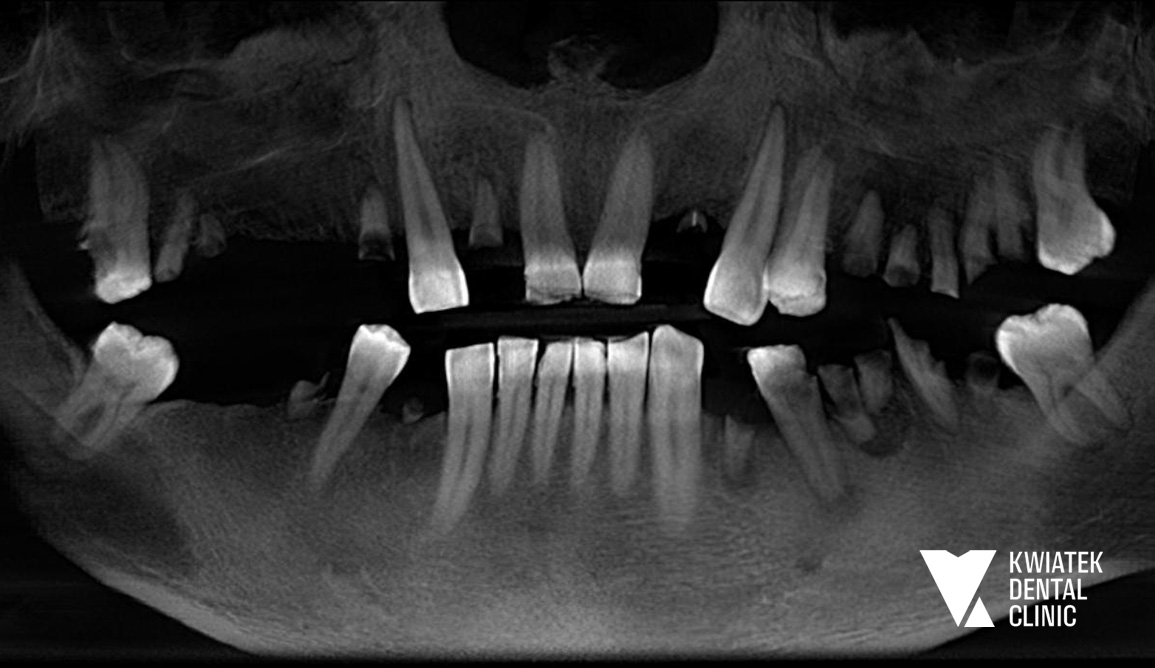

PRZED

W kolejnym etapie usunięto ósemki, a po wygojeniu tkanek wykonano skany cyfrowe i rejestrację zwarcia, aby precyzyjnie zaplanować rozmieszczenie implantów i kształt przyszłych koron. Podczas zabiegów zastosowano szablony chirurgiczne, co pozwoliło bezpiecznie i precyzyjnie wszczepić implanty zębowe.